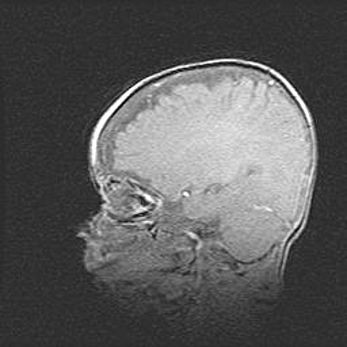

Церебральная ишемия II.

Возраст: 7 дней

Вес: 3350 г

Пол: женский

Окружность головы: 35 см

Срок гестации: 39 недель

Ишемия головного мозга – это состояние, которое развивается в ответ на кислородное голодание вследствие недостаточного мозгового кровообращения. У новорожденных она является следствием дефицита кислорода, что ведет к метаболическим расстройствам различной степени тяжести в тканях головного мозга, в том числе к развитию коагуляционных некрозов и гибели нейронов.